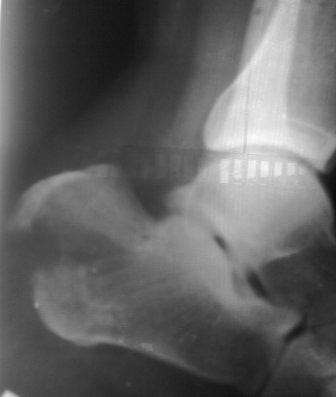

Здравствуйте, уважаемые коллеги. Обратился больной 29лет, через 25 дней после травмы с переломом обеих пяточных костей, слева без смещения, справа внесуставной отрывной перелом бугра пяточной кости (утиный клюв) в гипсовой повязке.

Р-снимки не качественные, снял на моб. на улице, поэтому прошу прошения!